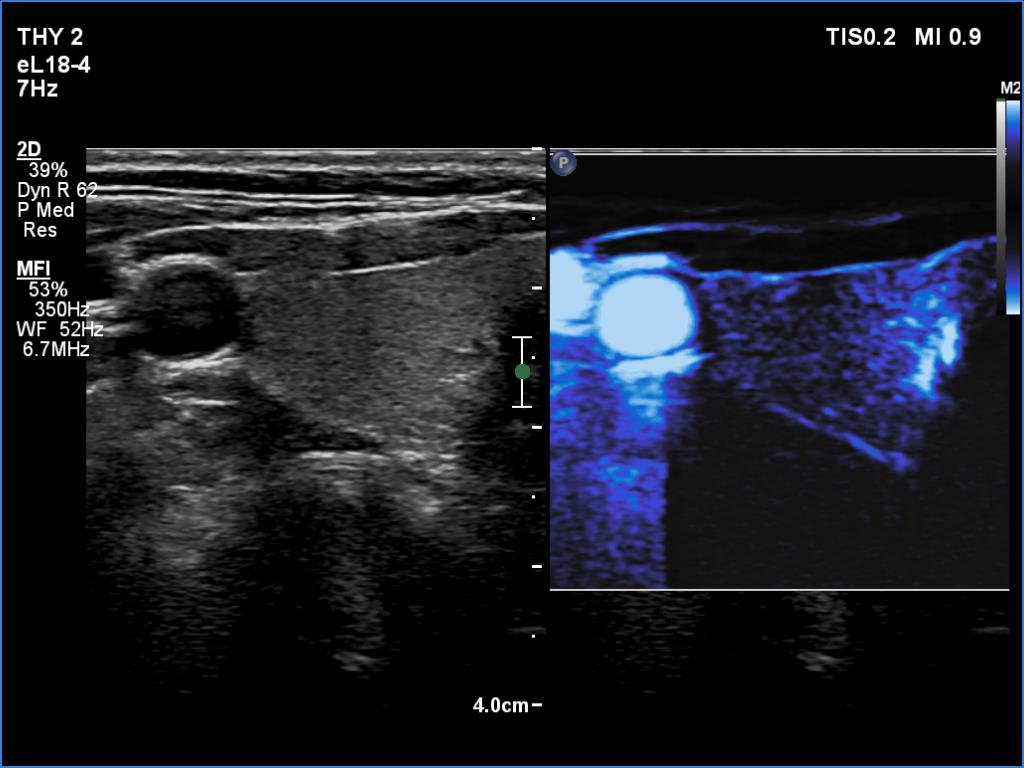

Ultrasonography. The thyroid was echonormal. There were no discrete lesions. The vascularity was average or slightly decreased. Microflow imaging has not revealed increased number of intrathyroidal vessels.